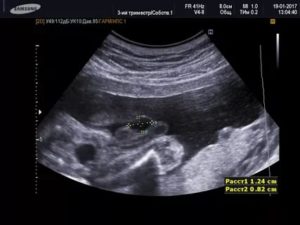

Ультразвуковые изображения мочевого пузыря демонстрируют кистозную структуру вдоль его передней части.

Отсутствие обильного кровоснабжения при допплерографии позволяет предположить доброкачественный характер кисты Первоначально пациенту выполняют абдоминальное ультразвуковое исследование, включая осмотр мочевого пузыря, при котором можно заподозрить аномалию развития урахуса с образованием кисты.